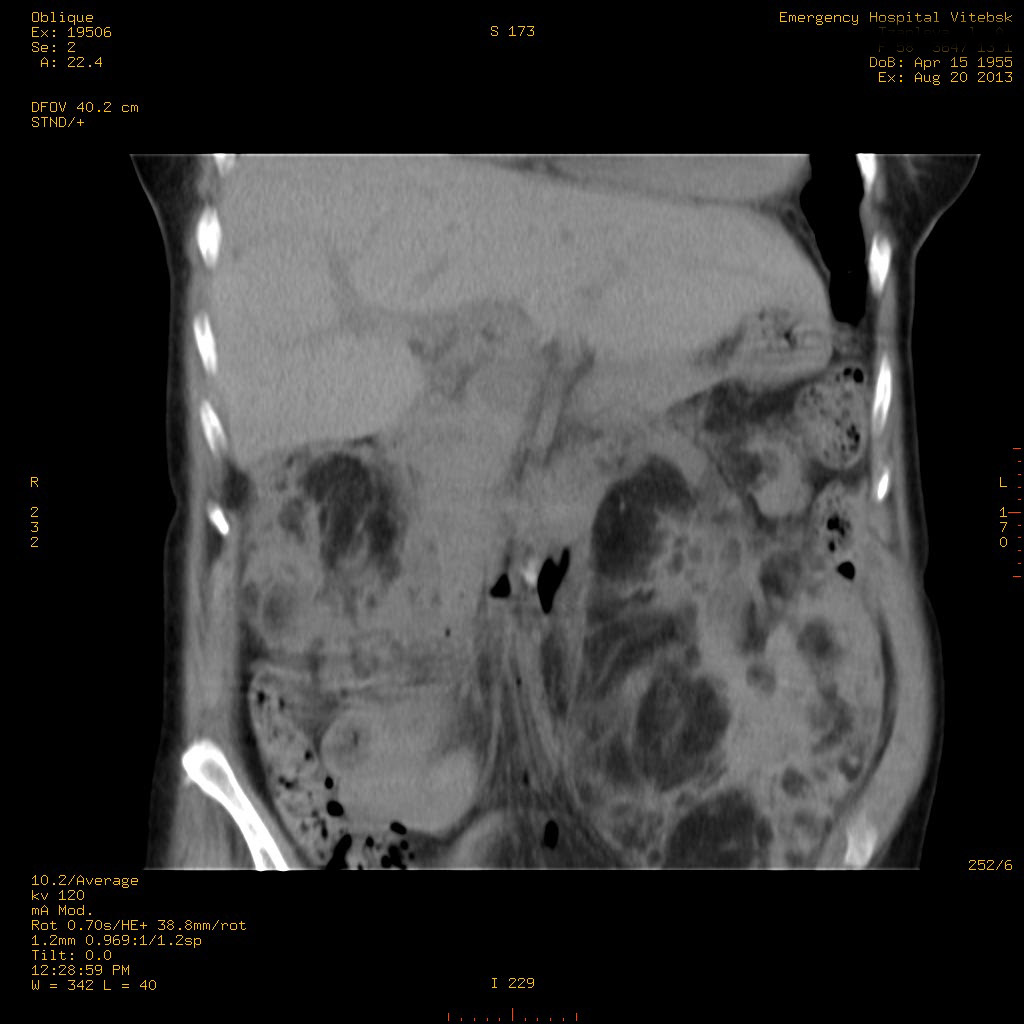

УЗИ почек - туберозный склероз

Пожилая женщина с нормальными мочевиной и креатинином.

Ангиомиолипоматоз почек , думаю компонент туберозного склероза.

Да, туберозный склероз.

Случай консультирован на кафедре радиологии Католического университета г.Лёвен (Бельгия) - зав каф. профессор Р.Оуен.